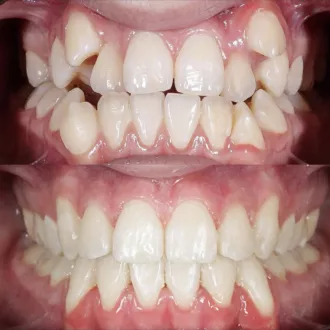

Результат коррекции металлической брекет-системой

Результат коррекции самолигирующей брекет-системой

Результат коррекции элайнерами

Результат коррекции керамической брекет-системой